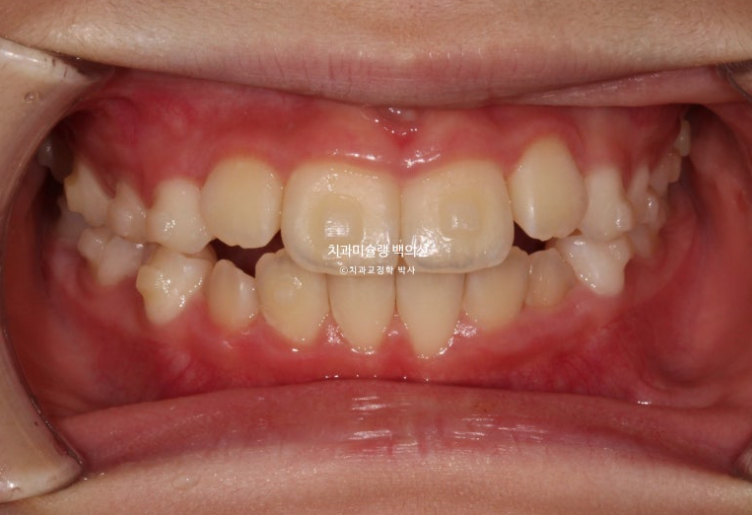

25년 6월 드디어 치료를 마무리 했습니다.

25.06

중심선은 잘 맞습니다.

아직 작은어금니들이 좀 더 내려와야 교합이 안정됩니다.

23.06~25.06

남아있는 유치는 없고 완전한 영구치열에 접어들었습니다.

나중에 2차교정을 안해도 될 정도가 되었습니다.